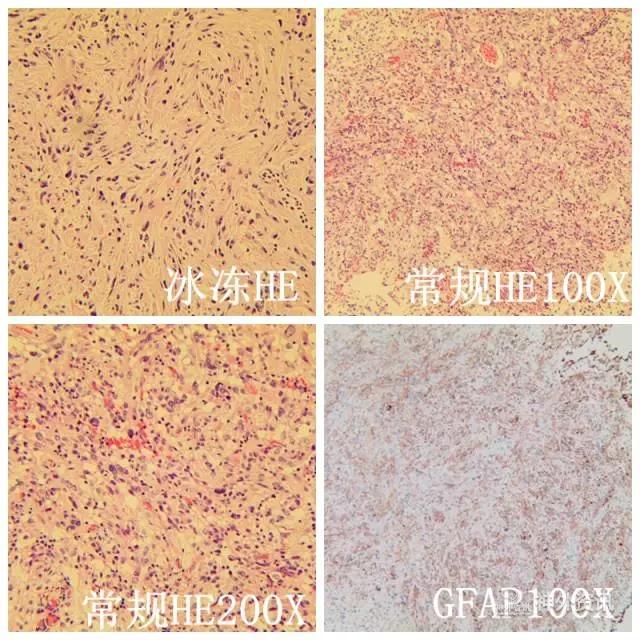

术后病理示:快速病理考虑星形胶质细胞瘤III级。GFAP(+),Oligo-2(+),S-100 (+),CD56(+),Vimentin(+),CK( -),Ki-67(10%)。

分子病理结果:MGMT甲基化阳性,IDH1/2野生型,TERT野生型,1p/19q未缺失,EGFR未扩增,EGFR VIII阴性,BRAF V600E突变型。最终病理考虑为多形性黄色星形细胞瘤(PXA)(图7)。

图7. 病理结果。